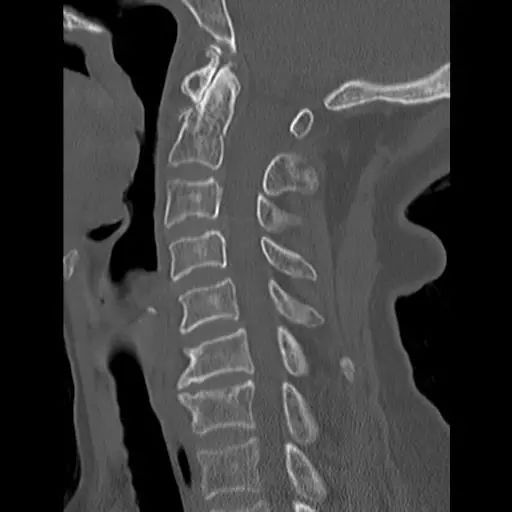

患者,男性,75岁,因外伤致颈部疼痛伴活动受限7天入院。患者入院前在当地医院确诊为:枢椎齿状突骨折Anderson-D’Alonzo分型Ⅱ型。

对于本患者来说,齿状突骨折后导致寰枢椎不稳,极易引起延髓或椎动脉损伤,严重者当场死亡。但患者同时合并严重胸腰椎后凸畸形,颈部后伸受限,不具备前路手术条件,这就给其治疗更增加了额外的困难。而由于手术部位延髓及椎动脉等血管神经密布,手术难度高、风险极大,稍有不慎,患者就会有生命危险。而患者家属在了解到手术的危险性后,曾自行到上级医院咨询专家,上级医院专家考虑围手术期死亡的风险,对于本例患者亦不愿提供手术治疗的机会。

经过全程监护和系统治疗,患者术后恢复良好,骨折解剖复位,复查X线及CT显示固定位置佳,术后3天下地行走,术后4天即出院回家休养。